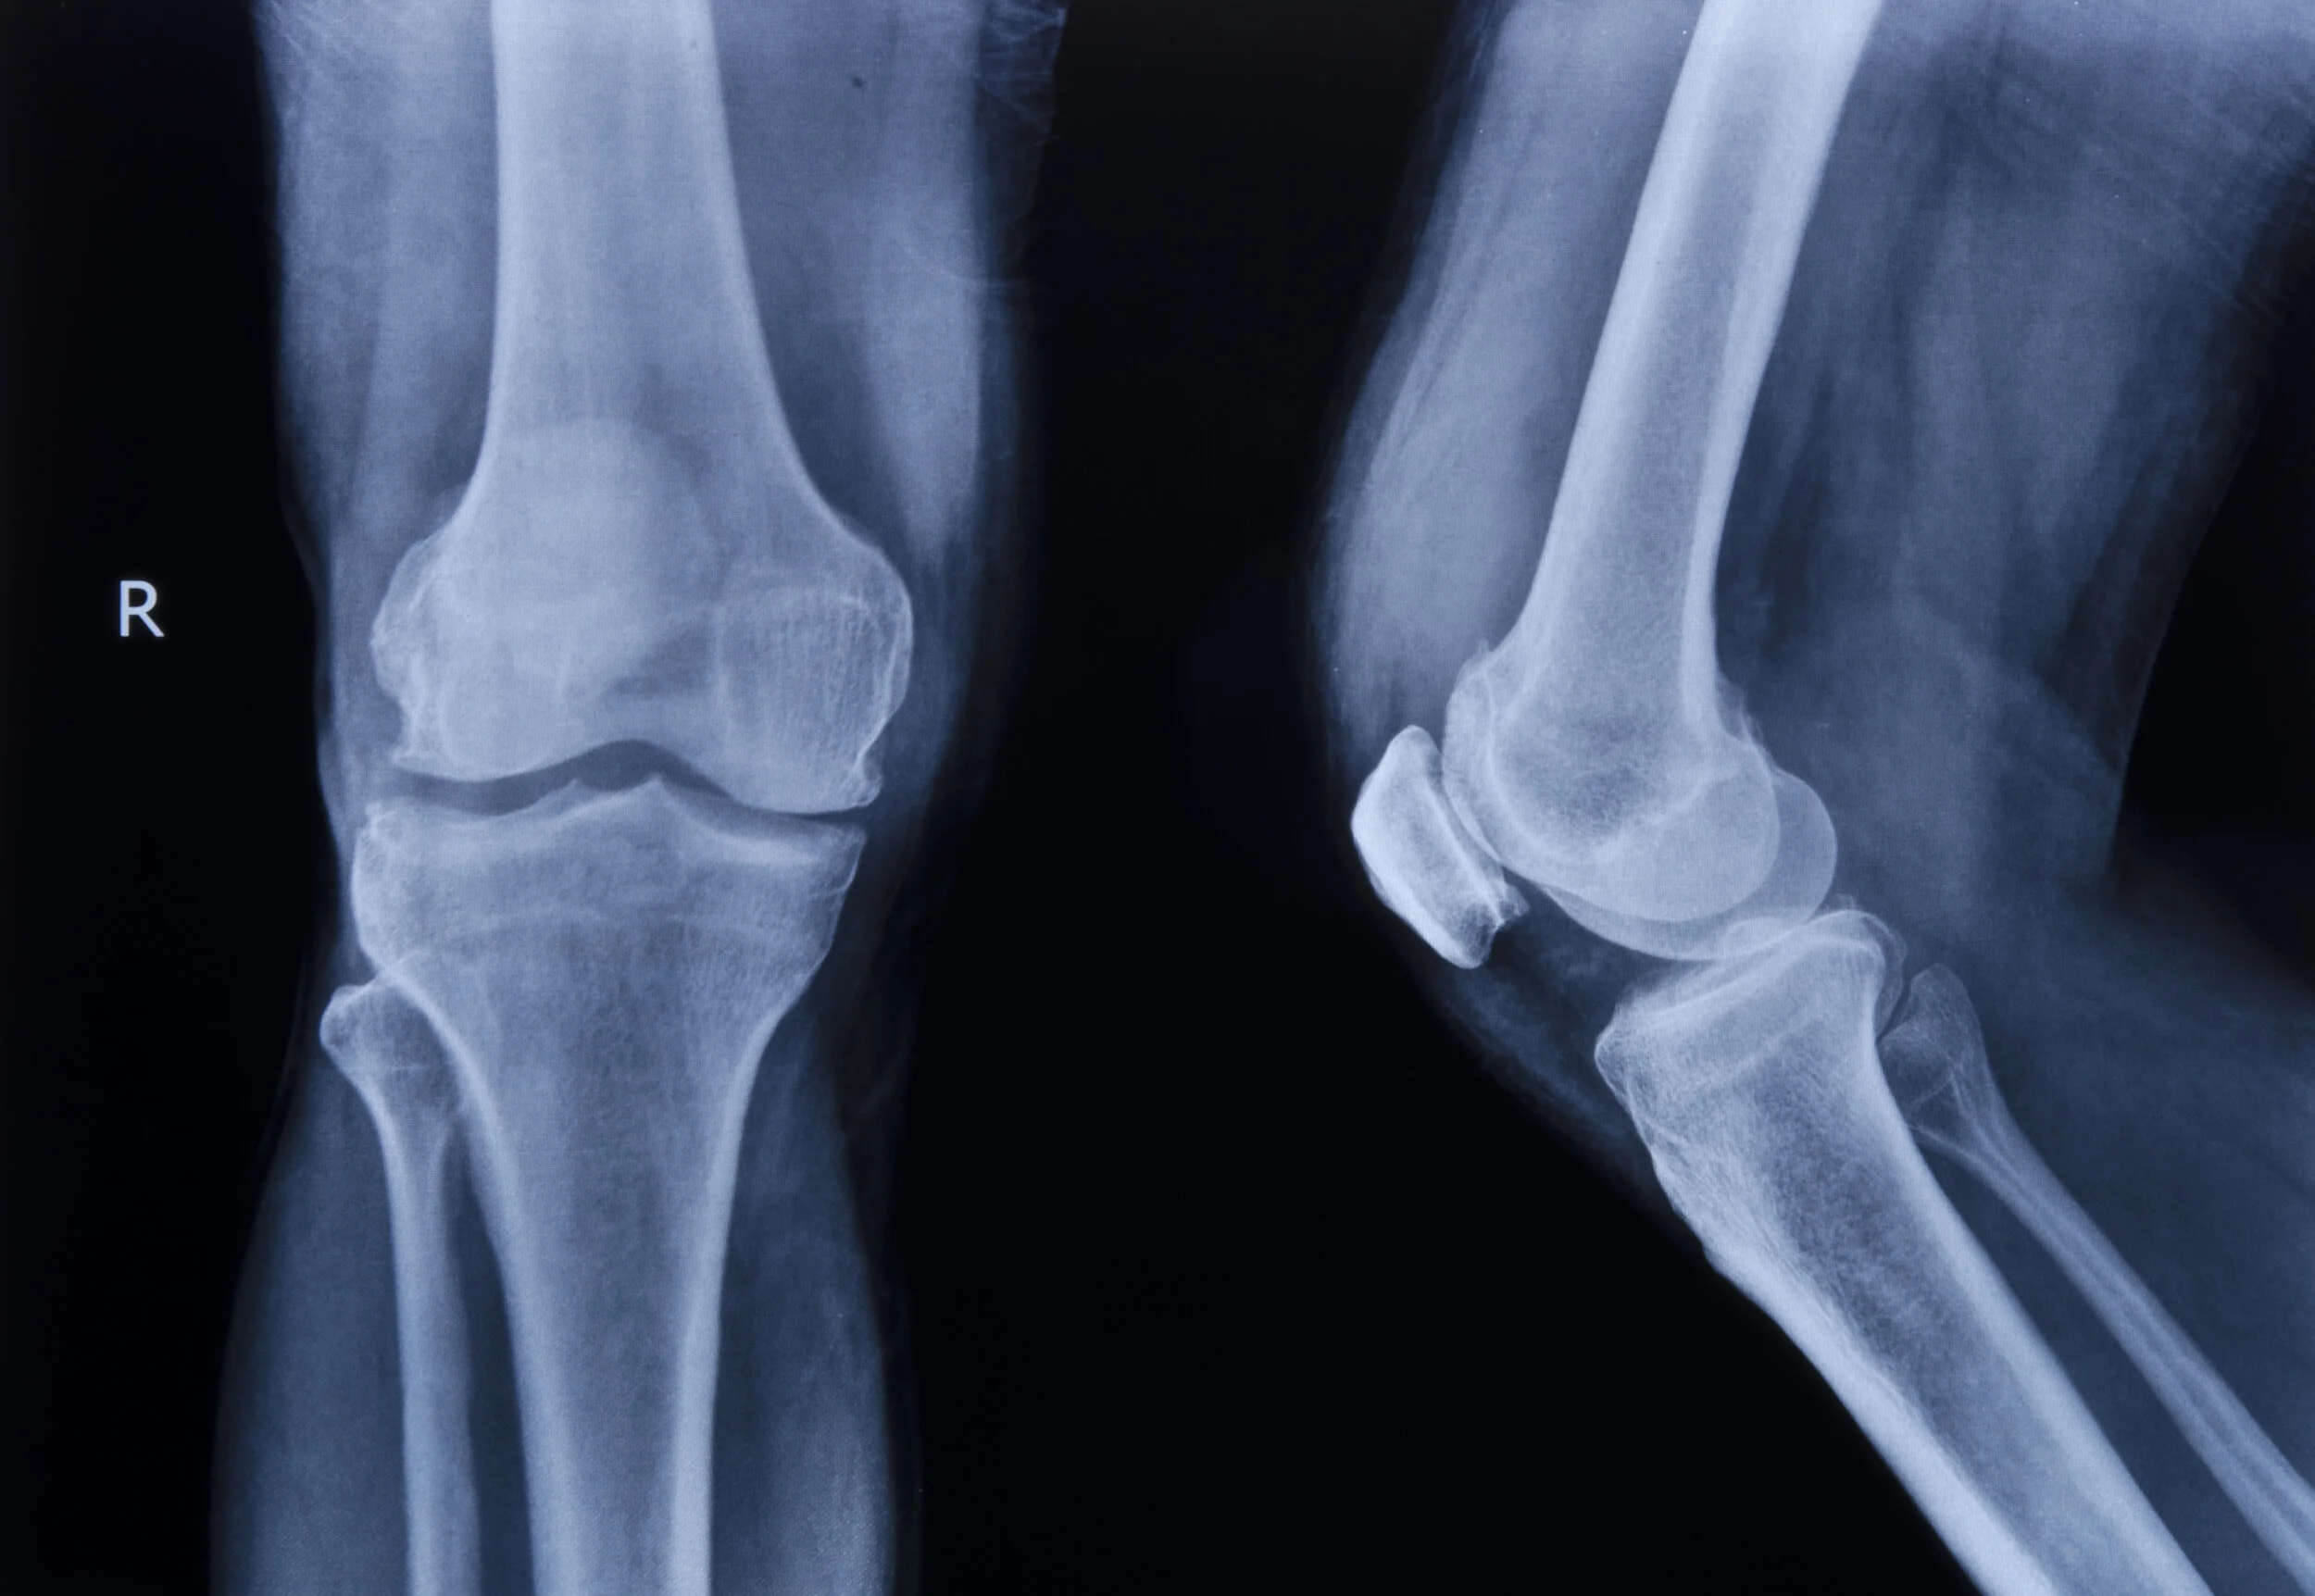

An X-ray of a patient's right knee seen from the front and side. (Photo courtesy: iStock)

For Black patients with osteoarthritis like Debra (a pseudonym to preserve her privacy), X-rays leave an incomplete picture of their experience. In the United States, many Black patients report feeling a much higher intensity of pain compared to white patients with similar X-rays, according to Dr. Staja Booker, a nurse scientist at the University of Florida’s College of Nursing who recounted Debra’s story. A study published in Nature Medicine earlier this year points to one explanation for this pain disparity: radiologists, grading the X-rays of both groups, have long used a standard metric called the Kellgren-Lawrence grade (KLG) to assess damage to joints. But derived from a pool of only white patients in the 1950s, this racially biased measure eclipses radiologists’ view of factors that may contribute to Black patients’ knee pain.

Pierson and her colleagues trained a computing system to predict how much pain a patient is experiencing by looking at X-rays of Black and white patients’ knees in the Osteoarthritis Initiative’s publicly available database. This neural network, which can recognize and model patterns in vast amounts of visual data, “is doing something fundamentally different than what a human does,” said Elizabeth Krupinski, a professor of radiology at Emory University interested in medical image perception, who was not involved in the study.

The neural network inspected tens of thousands of X-rays, pixel by pixel, eventually correlating certain physical features of the knee with patients’ reported pain. The system then created a heat map of the affected areas in the knee that may be causing pain in Black patients. The network was able to reduce the disparity in pain between races by nearly half.

The researchers gave the neural network few instructions except to take note of any patterns between the X-rays and pain reports. “It's a way to try and remove any bias” from radiologists’ readings of images and their interpretations of the Kellgren-Lawrence Atlas, explained Dr. Amanda Nelson, director of the Phenotyping and Precision Medicine Resource Core at the Thurston Arthritis Research Center in North Carolina, who was not involved in the study. Using this approach, the study authors stepped outside of traditional X-ray scoring to create a new measure.

The study authors were not able to discern exactly what the neural network is seeing. But Nelson suspects the algorithm may be able to see something human radiologists miss, such as the spots where bone is beginning to harden just below the surface of the cartilage. It’s possible those areas may be causing more pain for Black patients. Krupinski notes that human radiologists’ perception can be limited when it comes to discriminating textures in an X-ray and identifying small objects. “The challenge now is to find ways to convey to radiologists why [the neural network] is rendering that decision,” Krupinski said.